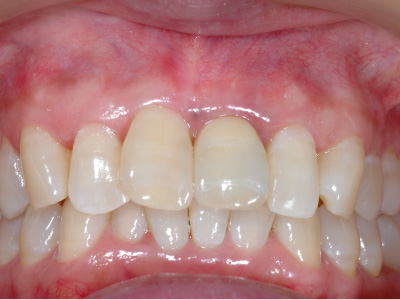

この時点では、歯と歯の間の「歯間乳頭」と呼ばれる歯茎が不足しているため隙間が空いており、インプラントの被せ物がいかにも人工物のように感じるため、審美的な仕上がりとはいえない。

そこで、上顎から切り取ってきた歯茎をインプラント周りに移植し、歯茎に厚みを持たせます。

歯茎の移植によって歯茎の隙間が埋まり、より自然な見た目を実現できました。

最終的に、周りの歯の色と形に調和するセラミックの被せ物をインプラントにセット。

歯茎との間に隙間がありませんし、色形のみでなく、すべてにおいて審美的に優れた仕上がりとなりました。